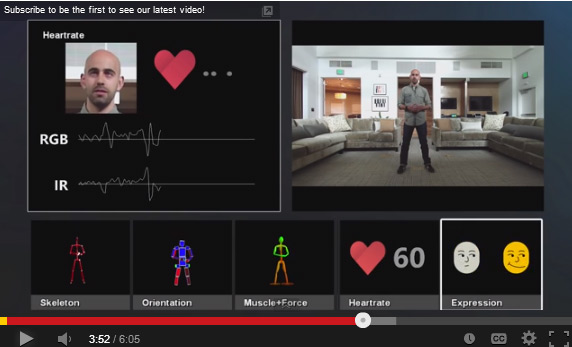

Epidural electrical stimulation involves implanting an electrode array along the lower part of the spinal cord, which ordinarily controls movement of the hips, knees, ankles and toes. Unlike similar approaches, the electrodes aren’t being used to directly stimulate the muscles. Instead, they act to reengage the spinal cord’s local nerve network, which doesn’t require input from the brain to carry out basic motor functions. The researchers surmised that this stimulation, combined with sensory input such as stepping on a treadmill could lead to movement.

In the latest study four candidates were chosen, Kent Stephenson, Andrew Meas and Dustin Shillcox. All four had experienced their spinal cord injuries at least two years prior to the study, and two of them were considered to have no chance of recovery.